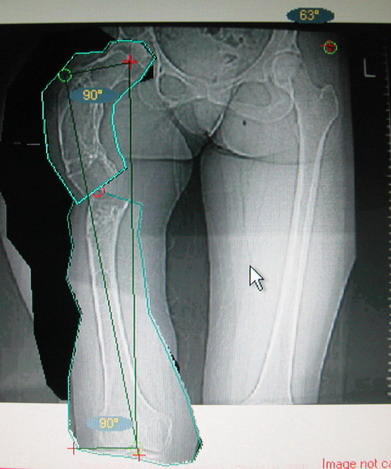

Моё мнение, что двойная остеотомия бедра с аппаратом Илизарова + Гексаподный механизм, или Тэйлора, В данной ситуации является методом выбора. Я очень извеняюсь за качество прилагаемых снимков, в которых я постарался отразить разницу междe одной и двумя остеотомиями бедра.